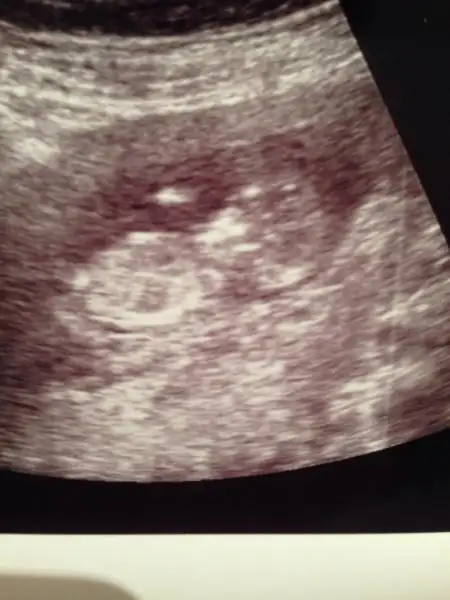

Eki Görüntüle 1173289 anlayan biri yorum yapabilirmi lütfennn!!!

iPhone 'den Kadınlar Kulübü aracılığı ile gönderildi